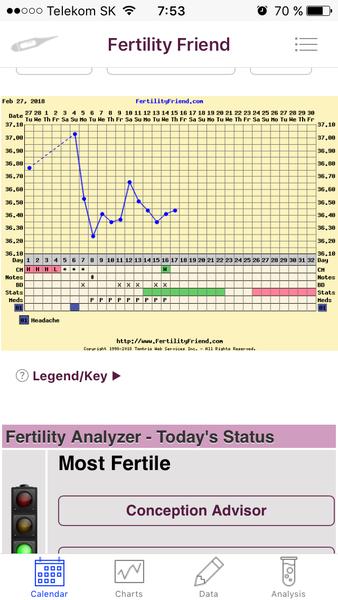

Grafy bazálnej teploty

Baby, nová téma o grafoch BT, ovulačných testoch, tehotenských testoch a hľadaní duchov je tu 🙂

Ak meriate bazálnu teplotu a zapisujete si hodnoty do grafov, ste na správnom mieste. Poradíme, pomôžeme, podporíme.

Grafy si môžete vytvárať na nasledovných stránkach:

www.fertilityfriend.com